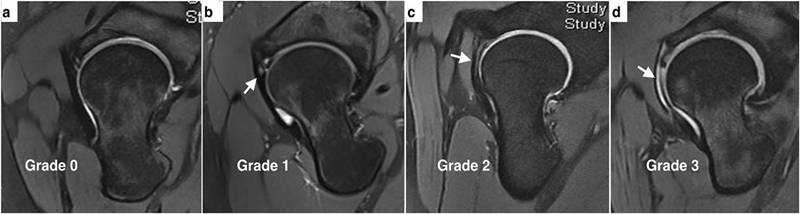

除厚度测量之外,也借助半月板的信号分级对前关节囊进行了内部信号分级。临床分为0~4级,正常表现是0级,出现点状信号为1级,出现线状信号为2级,出现断裂或者明显的贯通样分层为3级。